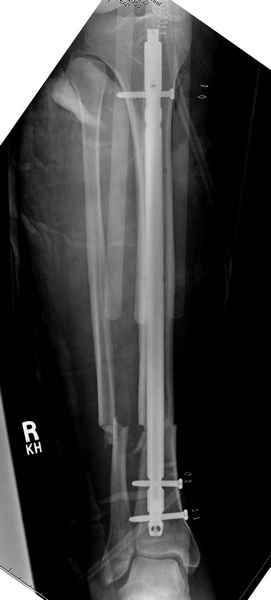

Больному с политравмой установлен наружный "spanning-bridging" фиксатор, после нескольких Irrigation&Debridment на фоне отрицательного посева из раны, через открытый участок установлен 4.5 mm Locking Plate.

На фоне фиксированного перелома бедра мероприятия по восстановлению мягкотканого покрова. Перелом голени зафиксирован после стабилизации бедра традиционным методом.

Антибиотические бусы могут быть оставлены в мягких тканях на длительный срок и не обязательно их удалять.